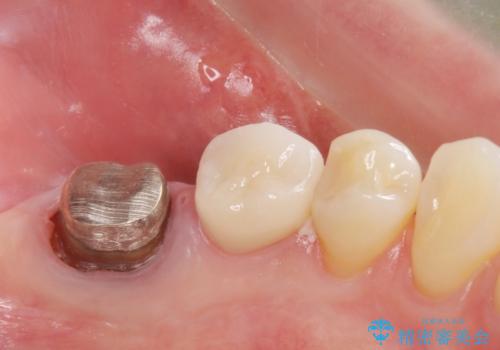

レントゲン上で根尖病巣が見られた場合

中の土台を外して根管治療を行わなくてはなりません。

また根尖病巣がなくて土台を変えたい(メタルから白の土台)場合

土台を外すと根管内が細菌感染する恐れがあるために根管治療をやり直す必要があります。